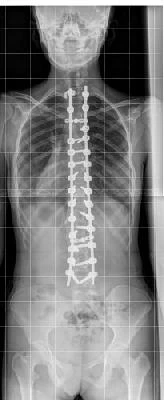

• علاج انحراف العمود الفقري

تحياتي لك..أختي لديها انحراف شديد في العمود الفقري في منطقة الكتف ولديها أيضًا قرص الخصر..أرسل لك الصور والشريط العصبي والعضلات..أريد أن أطلب رأيك في الطريقة التي يعاملون بها وما رأيك هو أفضل طريقة لعلاجه لأنهم مؤلمون للغاية الآن لدرجة أنهم لا يستطيعون القيام بأي تمرين ، وأيضًا الجلوس والوقوف والوقوف..لأنه سيكون حاملًا ، وبهذه المشاكل من غير المرجح أن نفعل ذلك..شكرا جزيلا لك..

مرحبًا ، هناك kyphosus شديد وإذا كان من الأفضل التحقق من ذلك..

مع عرض خدمتك. الدكتور.عانى أختي من العمود الفقري الشديد في منطقة الكتف وكذلك القرص القطني.أرسل الصور والخبراء إلى العصب والعضلات.أريد أن أرى رأيك في طريقة علاج علاجك، وفي رأيك، إنها أفضل طريقة لمعاملتها، لأن لديها الآن الكثير من الألم الذي لا يمكن القيام به من قبل أي رياضة ويجلس في الجلوس والوقوف والوقوف الكثير من الألم..لأنه يعتزم أن يكون حاملا، ومع هذه المشاكل، من غير المرجح أن نجعل هذا؟.شكرا جزيلا لشكركم.

مرحبا هو خلفي حاد، وفي حالة الألم تحقق بشكل أفضل.من المرجح أن تتطلب الجراحة التصحيحية.